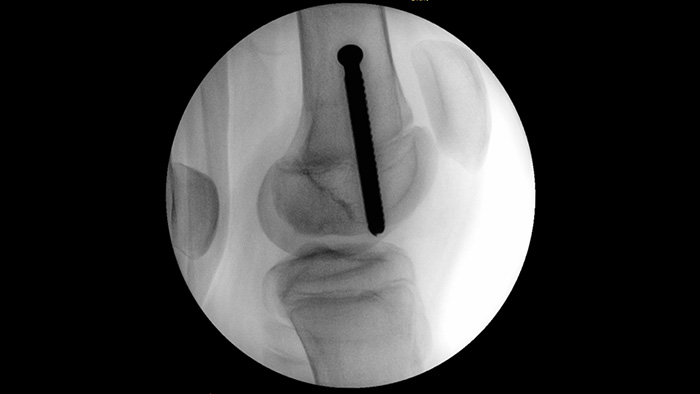

MetalSmart sluit metalen artefacten die worden veroorzaakt door metalen implantaten automatisch uit om, in vergelijking met systemen zonder metaaluitsluiting, een hogere beeldkwaliteit en efficiënte dosiscontrole te bieden voor orthopedische procedures en patiënten met metalen implantaten. BodySmart zorgt dat de beeldvorming vaker direct goed is en bevordert de dosisefficiëntie door het meetveld automatisch aan te passen aan het interessegebied.